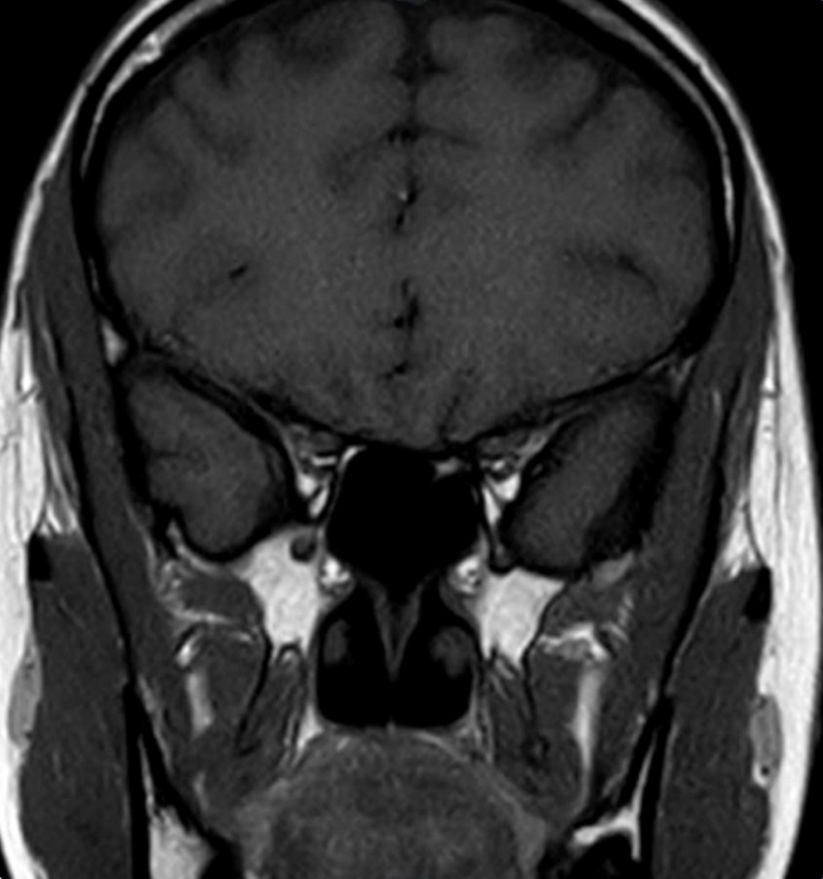

Computed tomography (CT) of the chest revealed multiple non-calcified subcentimeter pulmonary nodules (Figure 2). CT of the abdomen demonstrated a 7.5 × 10 × 10.9 cm lobulated, heterogeneously enhancing mass in the pancreatic body and tail (Figure 3A), invading the gastric fundus and encasing the splenic artery (Figure 3B), worrisome for malignancy.

Figure 2: Axial view of chest computed tomography with contrast revealing subcentimeter calcified pulmonary nodules.